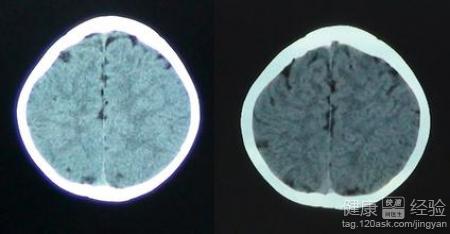

1我們必須知道並不僅僅高熱會引發驚厥,也有一類為無熱驚厥,常發生在一些非感染疾病,如顱內出血、腦水腫、癫痫、腦發育不全、腦積水、小頭畸形,以及營養障礙、代謝紊亂(如低鈣驚厥)、低血糖症、食物中毒、藥物中毒及某些農藥中毒等等。做CT可以幫我們明確病因,便於更好的護理。

3最後我們可以明確知道顱腦CT掃描不會影響孩子的大腦發育。CT掃描所用的X射線,理論上講對人體會有一定的生物效應,可以對身體的細胞產生一定損害。不過對於只做一次CT掃描,所用的輻射劑量是非常低的,完全在安全范圍之內,根本會對孩子的健康產生什麼影響,這個我覺得就不用過於擔心了。